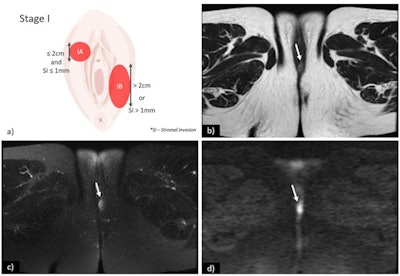

(a) Schematic illustration of International Federation of Gynaecology and Obstetrics (FIGO) stage I. Axial T2-weighted image (b), axial fat saturation T2-weighted image (c) and diffusion-weighted imaging with b-value = 800 s/mm2. (d) shows a vulvar tumor measuring < 2 cm, with pathologic proven stromal invasion of 4 mm, corresponding to FIGO stage IB. All images courtesy of Dr. Olivera Nikolić and Insights into Imaging."In spite of that, MRI staging of vulvar cancer is not used routinely in all cancer centres," the group's chair, Dr. Olivera Nikolić of the University of Novi Sad, Serbia, and colleagues wrote in an article published on 22 September in Insights into Imaging. "Standardising image acquisition techniques and MRI interpretation reduces ambiguity and ultimately improves the contribution of radiology to the staging and management of patients with vulvar cancer."